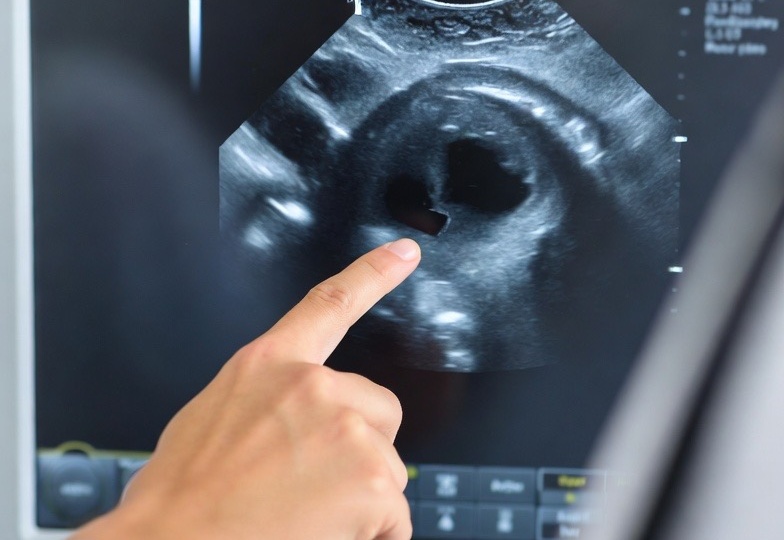

УЗИ сосудов показало бляшки: что это значит и почему это важно?

Наличие атеросклеротических бляшек в сосудах — это не медицинский эксперимент, а естественный, хотя и рискованный, процесс старения артерий. Исследования показывают, что их те или иные признаки можно обнаружить у большинства людей старше 50-60 лет. Важнейший вопрос не в самом факте их наличия, а в том, насколько они опасны, прогрессируют ли и требуют ли активного вмешательства. В этой статье мы на основе данных авторитетных медицинских источников разберем, что на самом деле представляют собой эти бляшки, почему УЗИ стало ключевым методом их выявления и как врачи подходят к оценке рисков для каждого конкретного человека. Атеросклероз — это хроническое заболевание, при котором на стенках артерий образуются жировые отложения (бляшки), состоящие из холестерина, кальция и других веществ. Они сужают просвет сосуда и снижают его эластичность, что в итоге может привести к серьезным осложнениям: от стенокардии до инфаркта или инсульта. Процесс начинается не в пожилом возрасте. Первые изменения